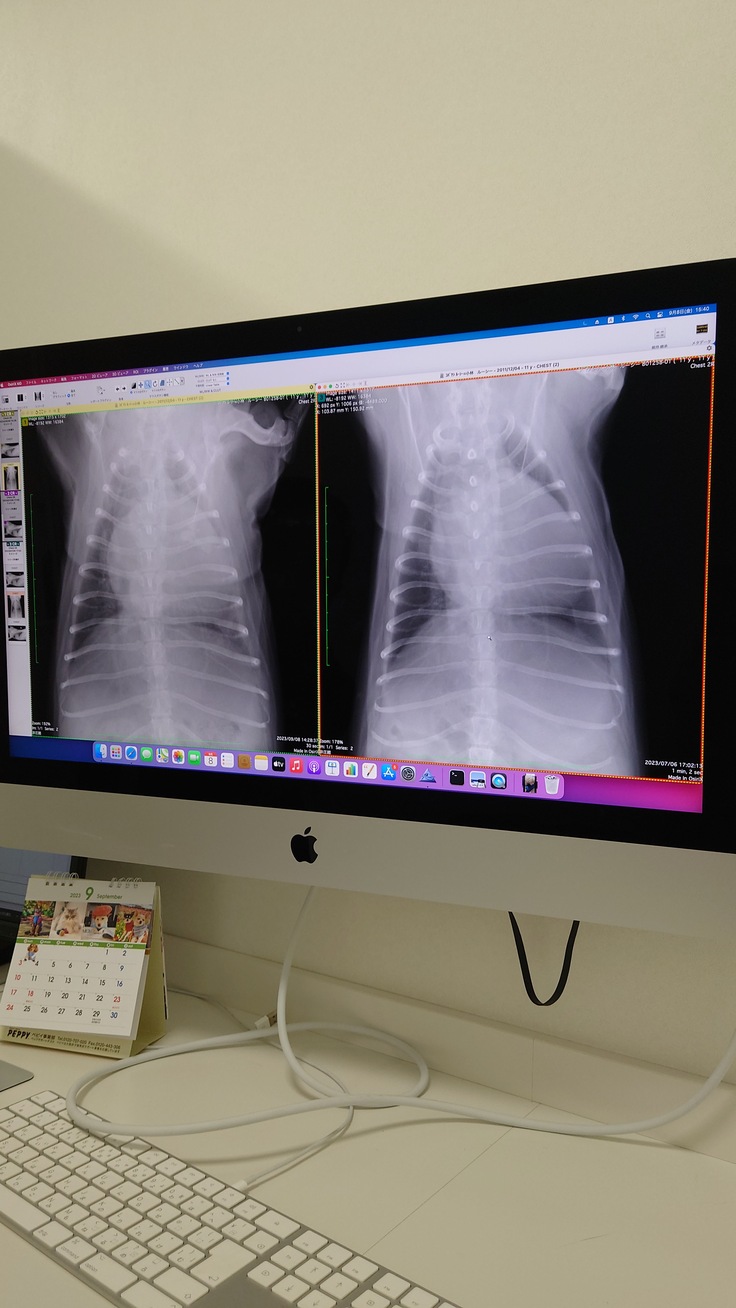

かかりつけ医の判断と同等、ステージD、肺水腫発症の判断は変わりません。

右が2か月前の肺、左が今日の肺、

水の量が多くなって白い部分が多く、

黒い部分が見えなくなっているのがわかります。

数日は酸素室生活、

利尿剤の注射などで様子をみて今後の対応を決めていく方針ではあります。